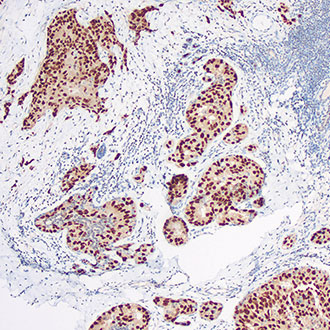

PMS2

PMS2 -